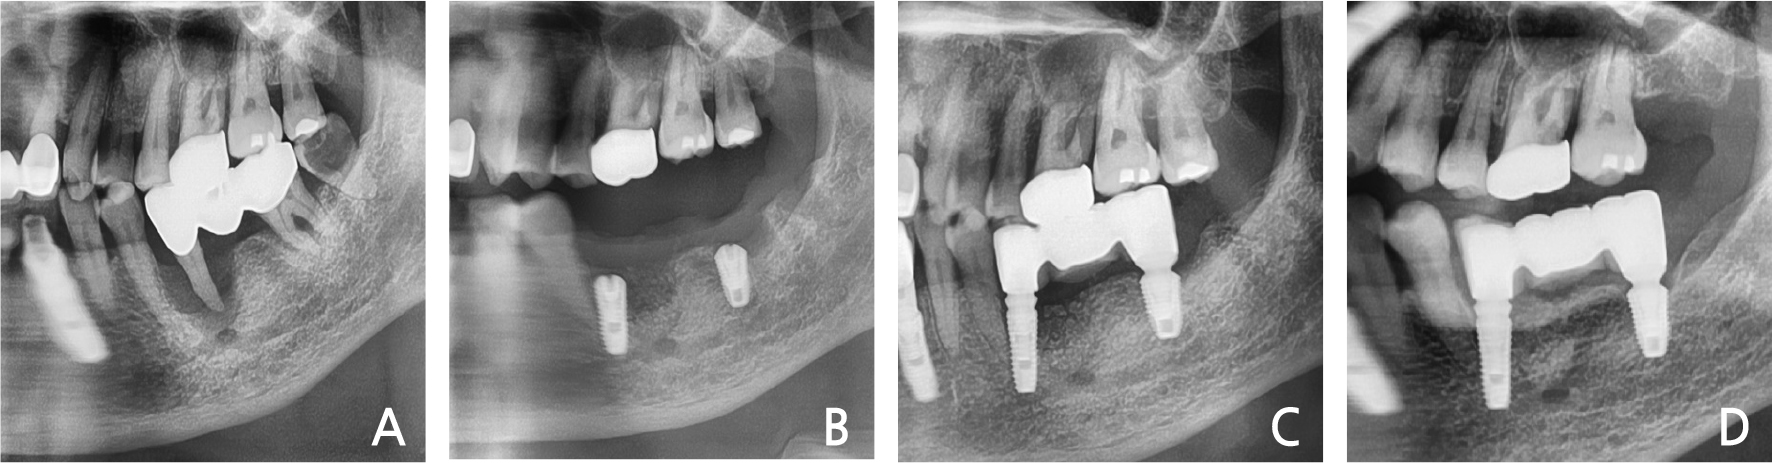

A 61-year old man presented to our clinic with severe pain in the right mandibular area.

He had no history of any systemic disease and was a smoker. Periapical pathology was observed on panoramic evaluation (Fig. 3A). Severe mobility was also noted. The right 1st molar was extracted under local anesthesia. After debridement, implantation with bone graft was performed at the defected bone area (Fig. 3B). The primary stability of the implant was attained by the apical 3-4 mm intact bone area. After 2 months, implant loading was performed (Fig. 3C).

After 3-years of follow-up, preservation of the gingiva and bone height was observed (Fig. 3D).

4. Case 4

A 56-year-old woman presented with discomfort and pain after a bite on the right mandibular molar that had been treated at a dental clinic. She had mild-controlled hypertension. Clinical and radiographic evaluations demonstrated severe bone loss and mobility in the mandibular right 2nd premolar (Fig. 4A). Under local anesthesia, the right mandibular 2nd premolar was extracted and immediate implant placement was performed with bone graft (Fig. 4B). The primary anchorage was gained from the linguo-apical 3 mm intact bone. After one month, loading was performed (Fig. 4C). The radiographic evaluation after 3-years of follow-up showed that the bone level was well maintained (Fig. 4D).

5. Case 5

A 68-year-old woman visited the dental clinic with the chief complaint of mobile left molar area. The patient exhibited severe mobility and purulent exudates in the left mandibular 2nd premolar – 2nd molar area. The radiographic view demonstrated a severe bone loss in the upper part of the mental foramen (Fig. 5A). The left mandibular 2nd premolar & 2nd molar were extracted, and immediate implant placement was performed with bone graft. The primary stability of the mandibular left 2nd premolar area was achieved by the mesio-lingual 3 mm intact bone (Fig. 5B). After one month, the dental restoration was fabricated (Fig. 5C). There have been no abnormal findings in the examination for the past 3 years (Fig. 5D).